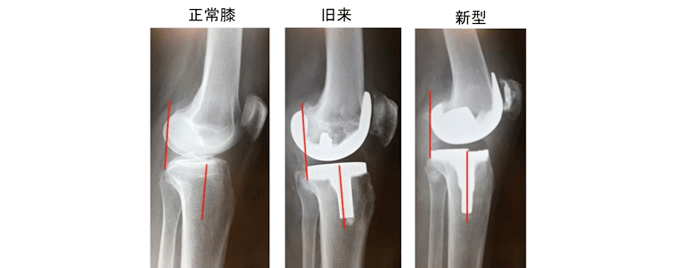

下の写真は正常膝・従来までのTKA・新しいTKAの側面像を比較したものですが、正常膝の大腿骨と脛骨の位置関係に比べて、従来型のTKAの大腿骨は後方に出っ張っているのがわかるかと思います。このタイプの TKAでは正常膝に近い大腿骨と脛骨の位置関係にあるのがわかると思います。BCS TKAではこのような正常膝に近い前後の位置関係を保つ事や人工関節の機械に工夫を加える事で、前十字靭帯の機能を再現しようとするもので、いい評価に繋がっています。

従来までの人工膝関節置換術(Total Knee Arthroplasty:TKA)の機械の種類には、上記の後十字靭帯を残したまま手術を行うもの、もしくは後十字靭帯を切除して人工関節で後十字靭帯の機能を代償しようというものでした。

従来のTKAの手術でも良好な成績がたくさん報告されています。しかしながら、TKAの手術後の痛みが残っているという患者さんが約20%もいるという報告もあります。その原因として、TKA後の患者さんの膝は、膝関節内部のもう一つの靭帯の前十字靭帯が切られたままの状態です。そのためTKA後の膝は前十字靭帯が機能していない膝であり、前十字靭帯が機能していないと、術後の膝関節の状態はグラグラと不安定な状態である事が術後の成績が不良な一因として報告されております。

このタイプのTKAは人工関節の機械に前十字靭帯機能を再現し安定性をもたらすと言われています。また、関節面の形状やポリエチレンの厚さを変える事によって、より正常に近い膝関節面と正常膝の動きを再現させるように人工関節がデザインされております。